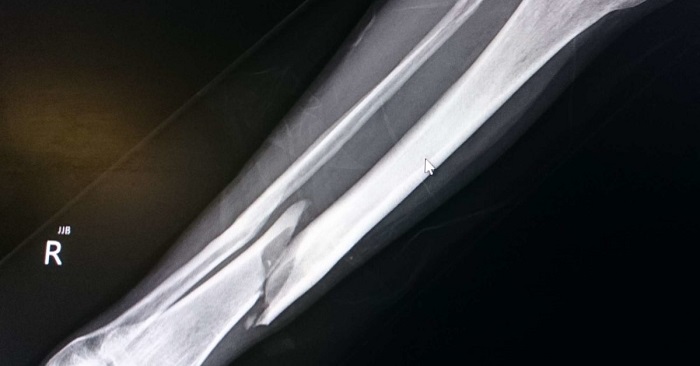

Image 2 – Fracture oblique du tibia inférieur

Les fractures obliques sont la fracture à un angle par rapport à l’axe transversal de l’os et s’étendent dans deux plans. Les fractures obliques sont le résultat d’un traumatisme indirect.

La radiographie suivante représente un homme de 47 ans qui a subi un traumatisme alors qu’il voyageait à vélo. La radiographie révèle une fracture du tibia de façon oblique et une comminution de la fracture était visible.